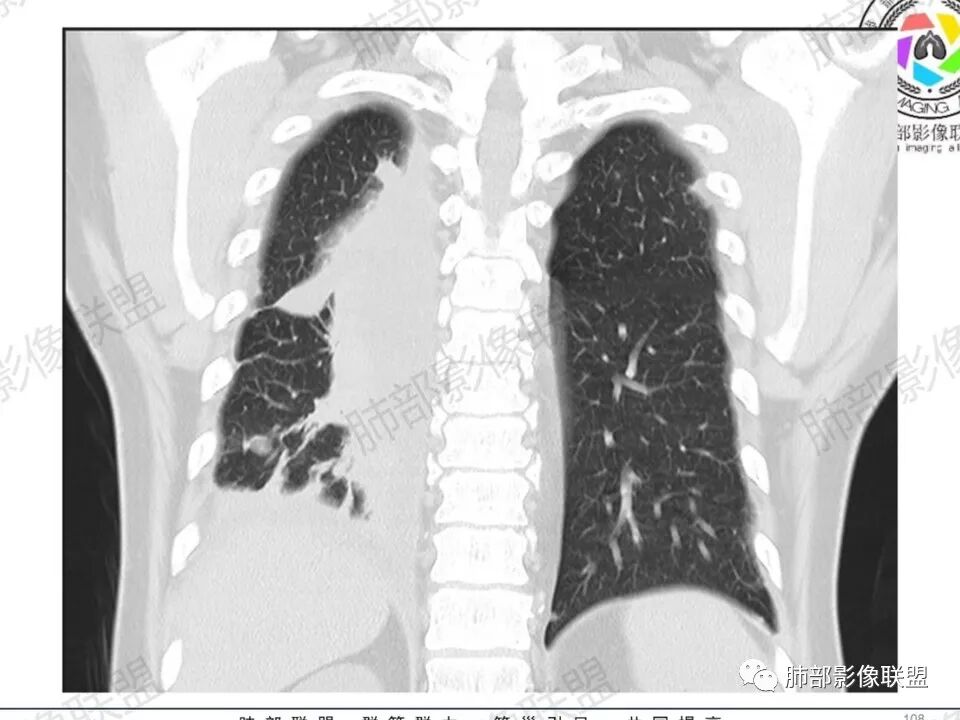

双肺多发结节,胸膜下为主,部分可见空洞。左肺上叶尖后段结节较大,分叶毛刺,周围可见长条索及小斑片影,内空洞比较光滑,内侧壁可见支气管通过。右肺下叶后基底段不张实变,后侧积液,右侧水平裂积液,右侧膈胸膜纵膈胸膜增厚积液,右侧侧胸膜肥厚,考虑1:一元金葡。2二元:金葡,左肺上叶结核。

感觉还是金葡入血形成SPE可能性较大,胸水+楔形影+胸膜结节

中年男性,左手中指及胸壁疼痛伴发热来诊,影像见双肺多发结节,胸膜下分布为主,部分结节可见空洞,边缘模糊。左肺上叶尖后段结节较大。右肺下叶后基底段不张实变,右侧叶间裂及右侧胸腔积液,右侧侧胸膜肥厚。考虑金葡菌感染,血播SPE。

两肺多发结节空洞,随机分布,右肺下叶部分病灶实变并胸膜腔少量积液,有皮肤破溃,手指疼痛,发热,考虑感染性变,金葡可能性大。